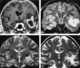

Temporal lobe astrocytoma

A brain tumor occurs when abnormal cells form within the brain. There are two main types of tumors: cancerous (malignant) tumors and benign (non-cancerous) tumors. [Source: Wikipedia ]